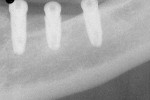

The osteotomy diameter was enlarged using standard drills up to 3.2-mm diameter available from the implant manufacturer and completed by visually centering the larger drills in the arc of the open guide sleeve. The final implant placement is illustrated in Figure 13 radiographically. Impressions were taken 3 months later, and three angled abutments (one 15º and two 25º) with minimal modification were used to restore the case (Figure 14 and Figure 15).